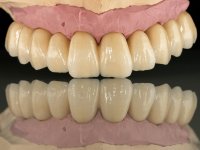

Realizada uma TAC, foi planificada a colocação de 6 implantes no maxilar superior. Foi decidida a colocação de dois implantes na zona dos incisivos centrais, dois implantes na zona dos caninos e dois na zona dos segundos pré-molares. A ausência de estrutura óssea na zona distal do primeiro quadrante implicava a realização de uma regeneração óssea no seio maxilar direito. A cirurgia foi realizada e após a colocação dos implantes foi feita a impressão para confeção de uma prótese provisória metalo-acrílica aparafusada para colocação em carga imediata no dia seguinte. O implante colocado na zona do seio maxilar direito não foi colocado em carga. Passados 6 meses foi realizada a impressão aos 6 implantes com técnica de moldeira aberta e foram confecionados os modelos de trabalho. Numa consulta seguinte foram montados os modelos de trabalho em articulador semi-ajustável utilizando o arco facial e a relação inter-maxilar obtida com a prótese provisória. Foi feita uma muralha de silicone sobre a ponte provisória com o objetivo de orientar o trabalho laboratorial. Realizada a infra estrutura metálica aparafusada esta foi provada em boca e finalmente após colocação de cerâmica o trabalho foi colocado definitivamente. Como passaram vários meses após a realização da primeira TAC foi feita uma segunda para planificar a colocação de implantes no 4º quadrante. Colocaram-se 3 implantes na mesma sessão em que foi feita a extração dos pilares da ponte. Estes implantes foram posteriormente reabilitados com uma ponte metalo-cerâmica aparafusada de três elementos.